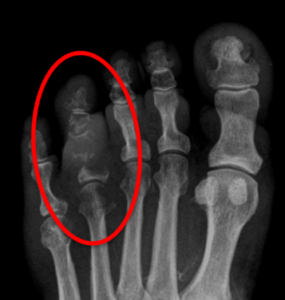

Radiografias

Radiografia é um exame que avalia a conformidade óssea. Sabemos que para vermos uma alteração real no RX é necessária uma destruição óssea de aproximadamente 30% do osso. Assim, como a velocidade de destruição óssea das bactérias usualmente são lentas, a osteomielite aguda não é possível de ser identificada em radiografias, pois nesta fase ainda não há destruição óssea, apenas inflamação. Portanto, as radiografias conseguem dar o diagnóstico apenas da osteomielite crônica,